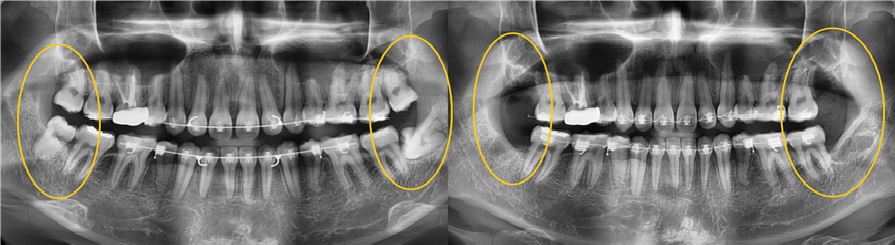

치료전후사진